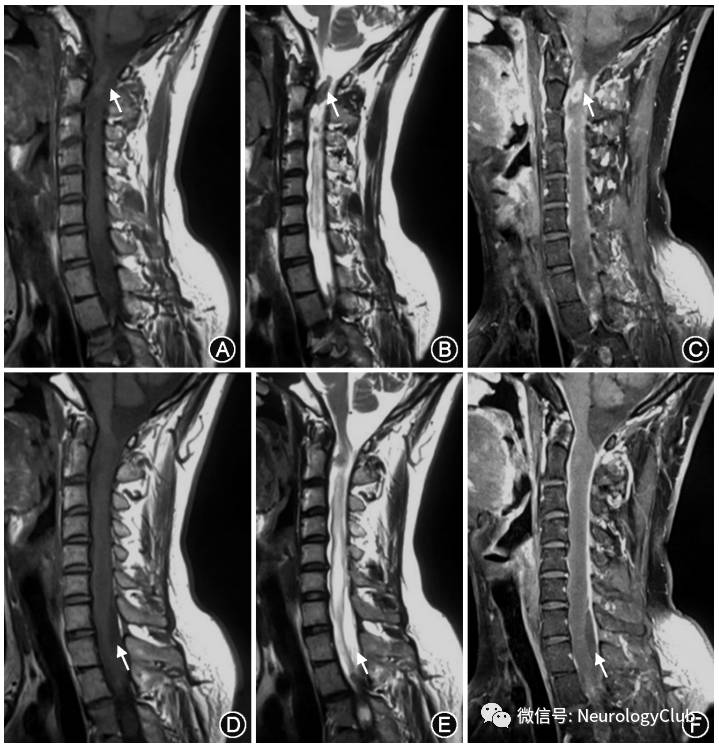

患者男性,28岁,农民,有羊接触史,因“双下肢无力14个月,加重4个月”于2017年1月10日收入我科。患者于2015年11月无明显诱因急性起病,表现为双下肢无力,不能行走,言语模糊,有一过性幻觉,反应慢。随后患者在当地医院查出布鲁杆菌阳性,并给予抗菌治疗、多西环素100mg静脉注射2次/d。治疗半个月后,患者双下肢无力现象得到缓解,可以下床拄拐走路,但有小便费劲,遂出院。患者于2016年9月病情加重,再次出现双下肢无力、发沉,无法自行走路,为求进一步诊治入我院。患者自患病以来无发热,无头痛头迷,无意识障碍,无恶心呕吐,无视物不清,无视物成双,无耳鸣,无饮水呛咳及吞咽困难。精神状态可,饮食睡眠可,大便无知觉,小便尚可,近期体重无明显减轻。入院体检:意识清楚,语言流利,双侧瞳孔等大同圆,对光反射灵敏,颈强阴性。双上肢肌力、肌张力正常,双下肢肌力均为IV级,肌张力正常。双侧肱二头肌反射亢进,肱三头肌、膝腱、跟腱反射正常。双侧巴宾斯基征阳性。深浅感觉未见确切异常。辅助检查:颈椎MRI平扫+增强示颈胸髓段蛛网膜下腔内见不规则结节状略短T2信号结节(图1A、B),增强后可见环状,结节状明显强化,肉芽肿形成可能大(图1C);脊膜增厚,蛛网膜局限黏连扩张,颈髓及T1-4水平胸髓内水肿,炎性改变(图1D、E),增强后未见明显强化影(图1F)。腰椎MRI平扫+增强示:L5-S1水平椎管内可见多发结节状长T1、短T2信号结节影(图2A、B),增强扫描后可见较明显强化(图2C);马尾神经增粗强化。颅脑MRI平扫+增强无异常,肺CT平扫见右肺及胸膜陈旧性病变。床旁心电图示:窦性心律,I度房室传导阻滞,中度右偏电轴。检验结果示:血尿常规及肝肾功能未见异常,肿瘤标志物未见异常,虎红平板凝集试验显示血清布鲁杆菌病抗体阳性,滴度1∶200(+)。

图2:患者腰椎MRI平扫 +增强,箭头所示处L5-S1局限后突,硬膜囊受压,马尾神经增粗;L5-S1水平椎管内可见多发结节状结节影,T1呈低信号,T2呈低信号(箭头,A、B) ;增强扫描后结节影可见较明显强化(箭头,C)